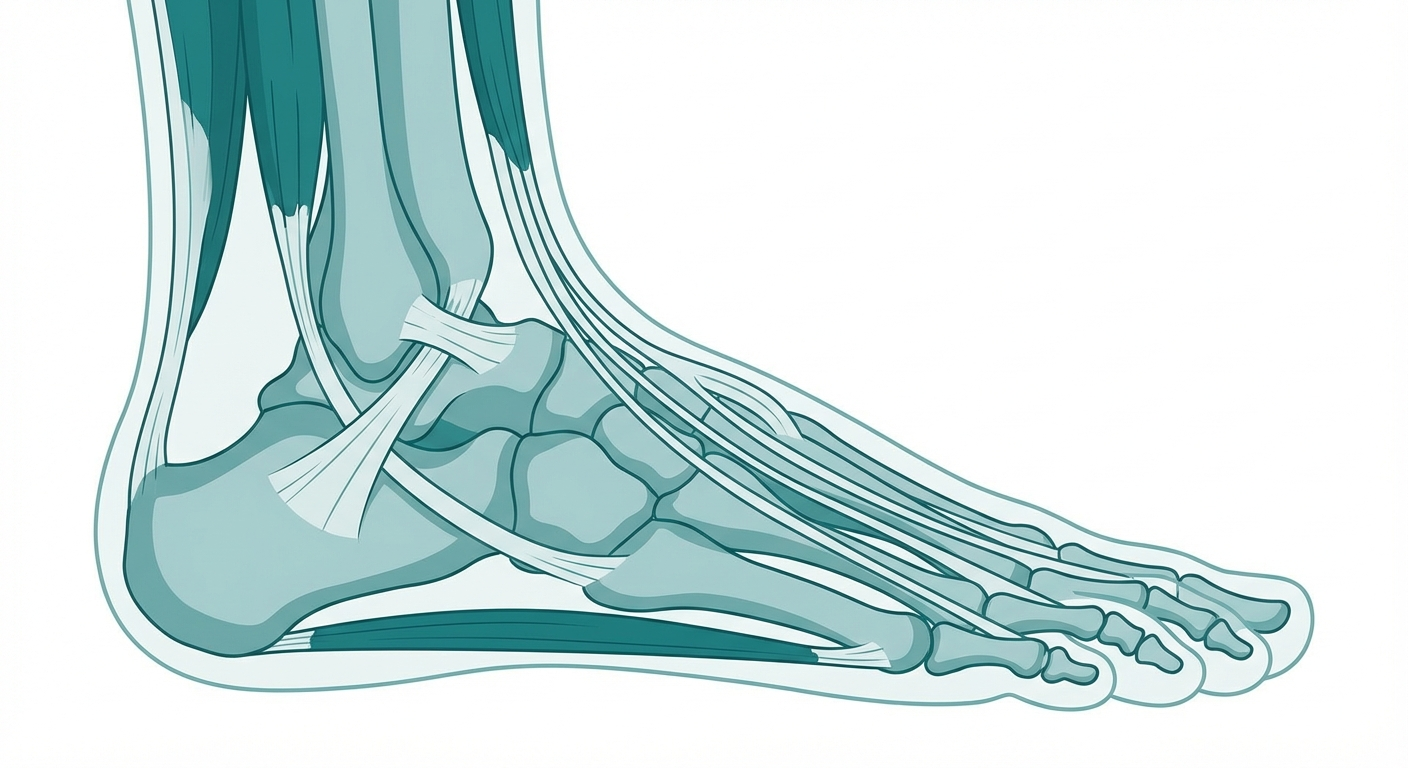

Foot & Ankle Pain

Foot and ankle pain can sideline you from activities you love. Whether it's that first painful step in the morning or lingering ankle instability, evidence-based exercises can speed your recovery.

Foot & Ankle Pain: Causes, Exercises & Treatment

Foot or ankle pain holding you back? Learn the most common causes, best exercises, recovery timelines, and when to see a physical therapist.